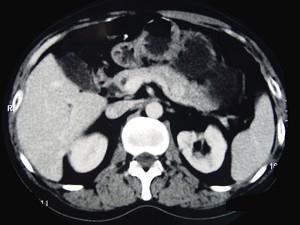

问题 男性,57岁,1年前无明显诱因反复出现嗜睡及发作性神志不清,进食糖水或甜品后症状即缓解,腹部CT检查如下图,最佳的诊断是 ( )

选项 A、胃泌素瘤 B、舒血管活性肽瘤 C、胰岛细胞瘤 D、胰腺转移瘤 E、胰腺癌

答案 C